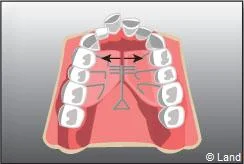

De plus, il est opportun de corriger très tôt certaines malpositions. Les appareils généralement utilisés sont amovibles avec une armature en résine, mais peuvent aussi être fixes à l’aide de bagues sur les premières molaires définitives.. Suivant leurs conceptions et la manière dont ils sont portés, ils auront une action sur la position des dents mais aussi sur la croissance.